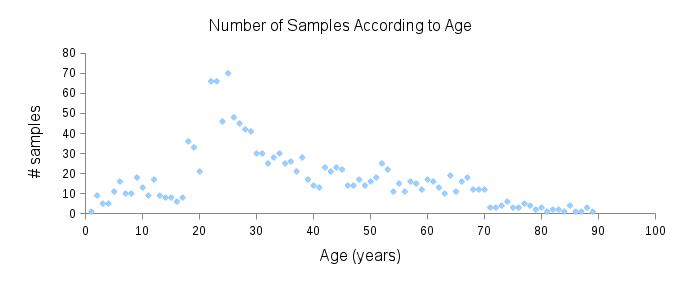

Toolsets to define normal appearance and therefore both assist with planning of surgery and define optimal outcomes from a range of surgical interventions are currently either crude or lacking. Therefore, the unit collected a large, high quality 3D image dataset of 1523 human heads. An example is given in Fig. 1 showing the 3D channel only on the left, and the 3D data with texture pasted on on the right. The data was collected over well-conserved demographics, and an age range of 1 to 89 years, see Fig. 2. The dataset was collected with the aim of developing a normal equivalent of the human cranium and face in order develop the tools to enhance patient experience following surgery. We plan to make the dataset publicly available in the near future.